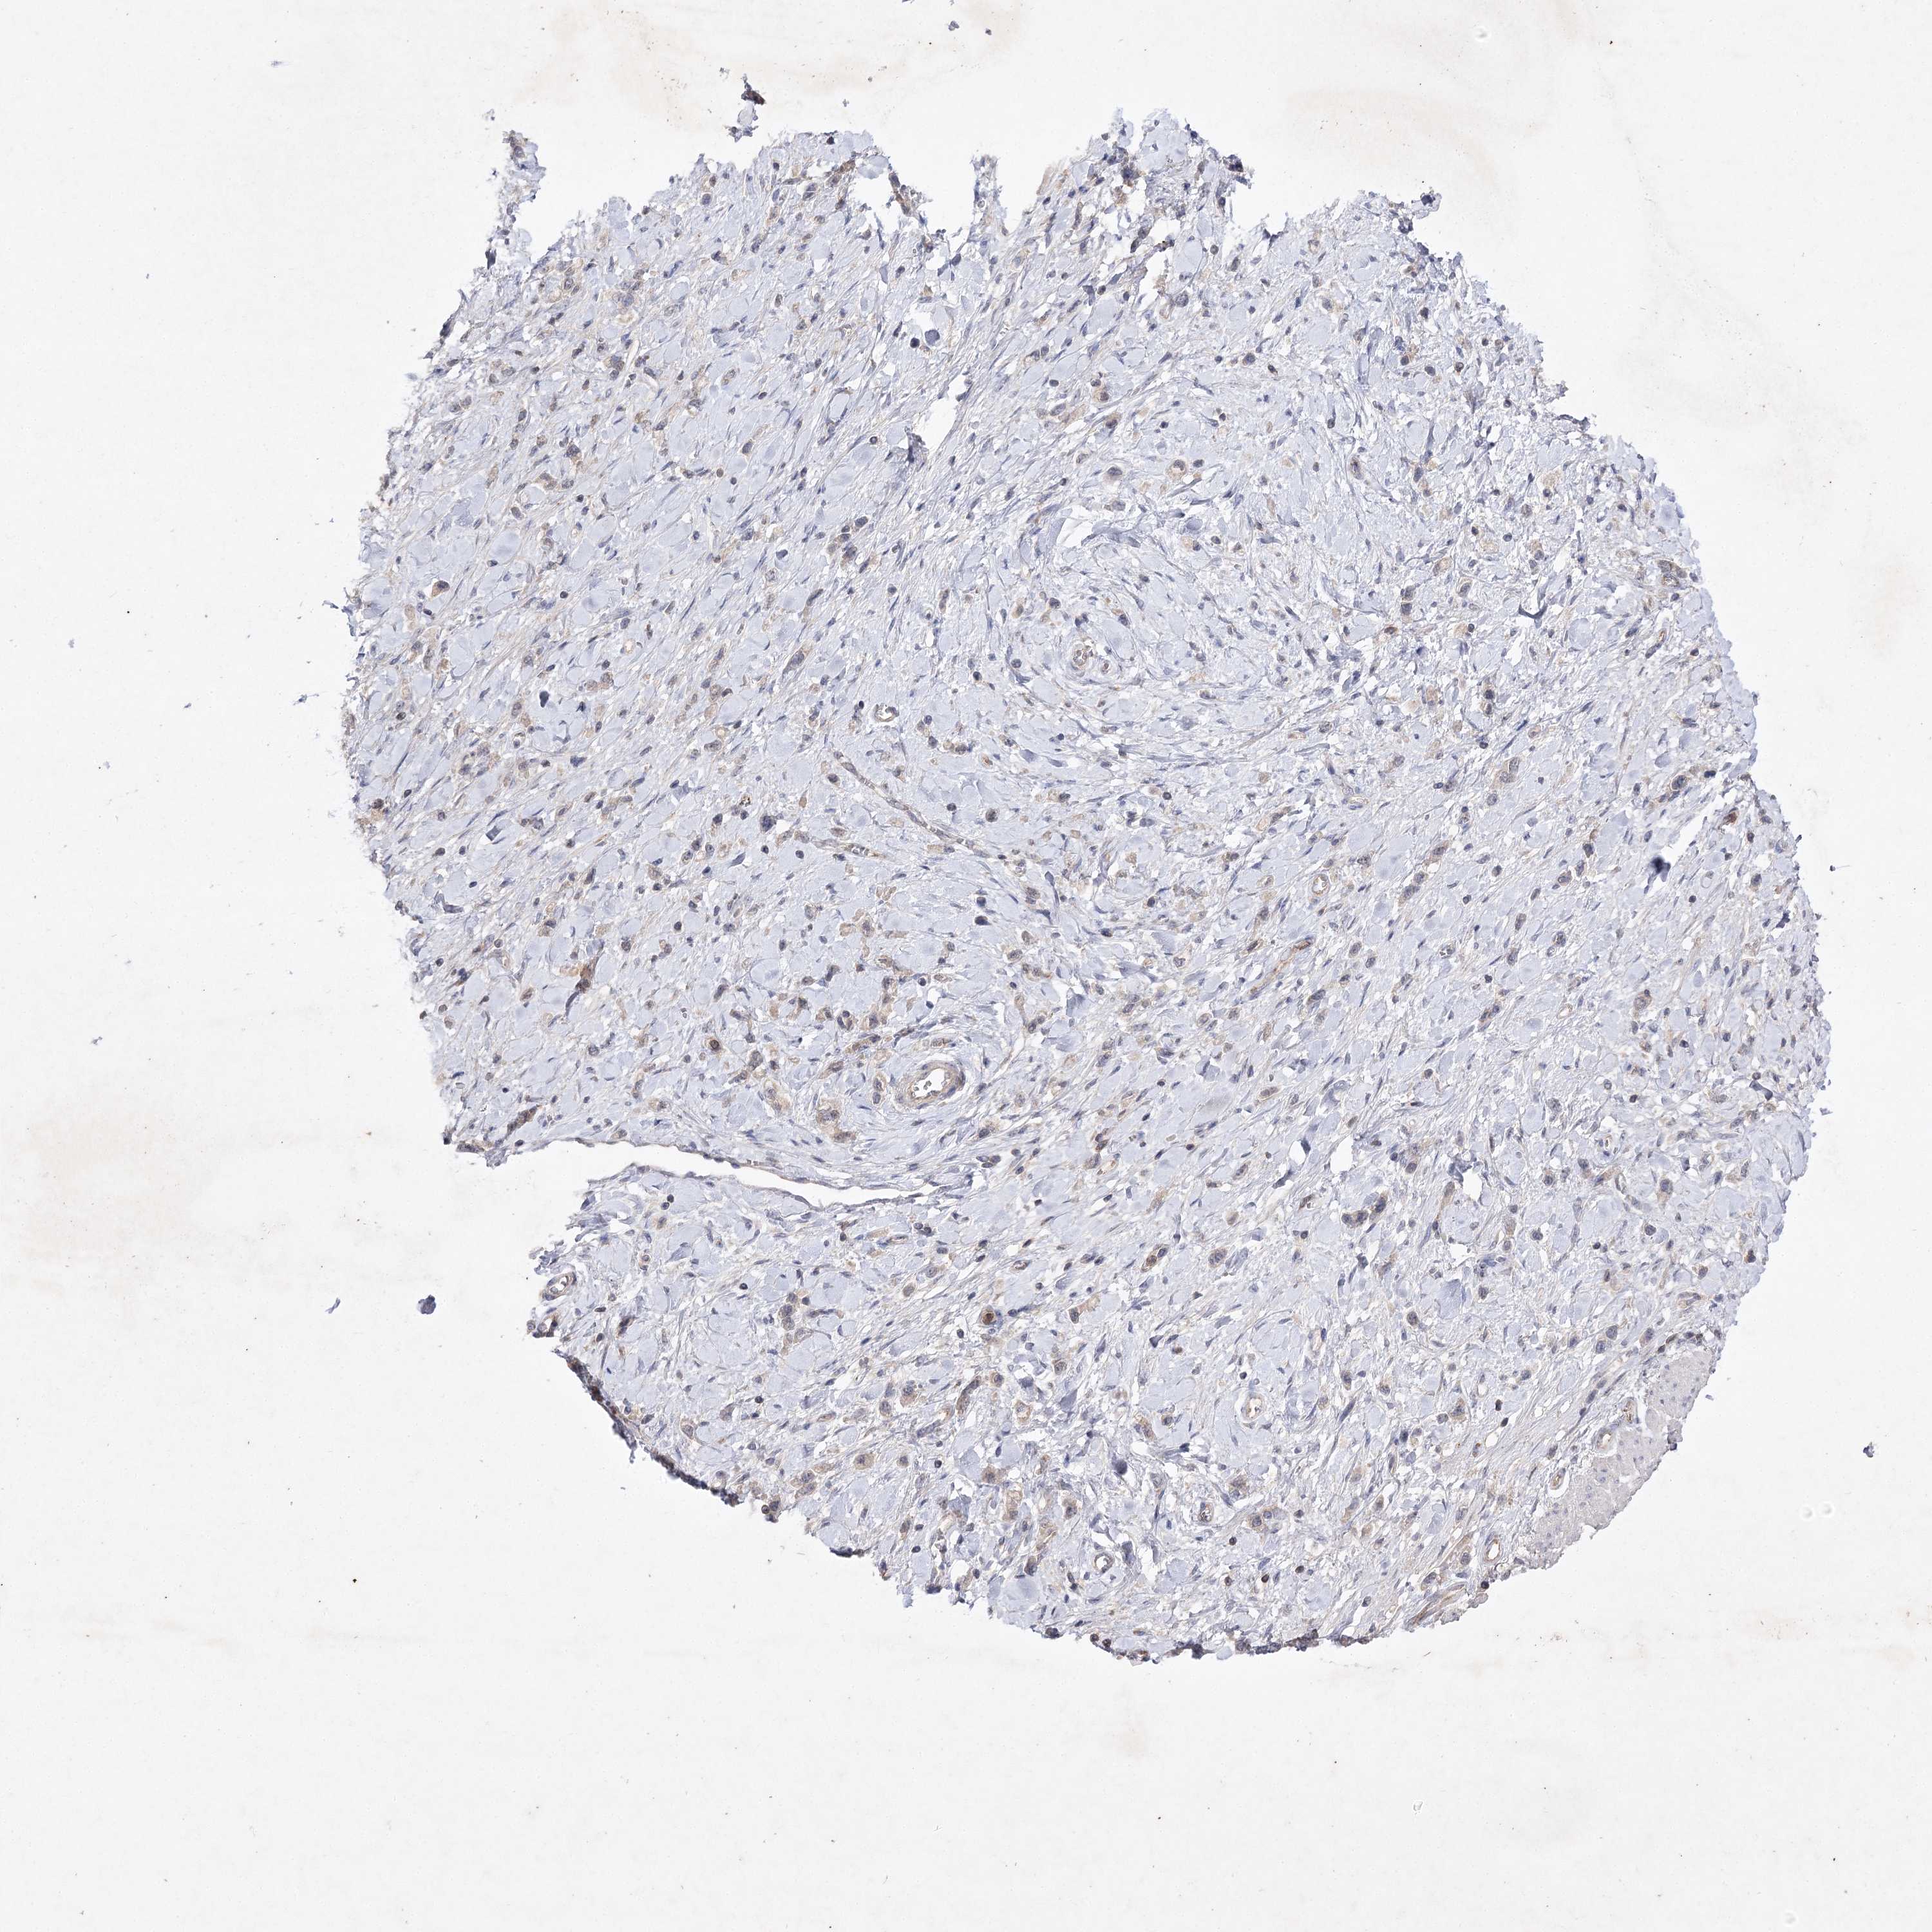

STOMACH CANCER - Protein expressioni

A mouse-over function shows sample information and annotation data. Click on an image to view it in a full screen mode. Samples can be filtered based on level of antibody staining by selecting one or several of the following categories: high, medium, low and not detected. The assay and annotation is described here.

Note that samples used for immunohistochemistry by the Human Protein Atlas do not correspond to samples in the TCGA dataset.

Antibody stainingi

Antibody staining in the annotated cell types in the current human tissue is reported as not detected, low, medium, or high, based on conventional immunohistochemistry profiling in selected tissues. This score is based on the combination of the staining intensity and fraction of stained cells.

Each image is clickable and will lead to virtual microscopy that enables deeper exploration of all samples and also displays staining intensity scores, fraction scores and subcellular localization as well as patient and tissue information for each sample.

Antibody HPA038337

Antibody CAB010421

Antibody CAB018545

Staining

Adenocarcinoma, NOS